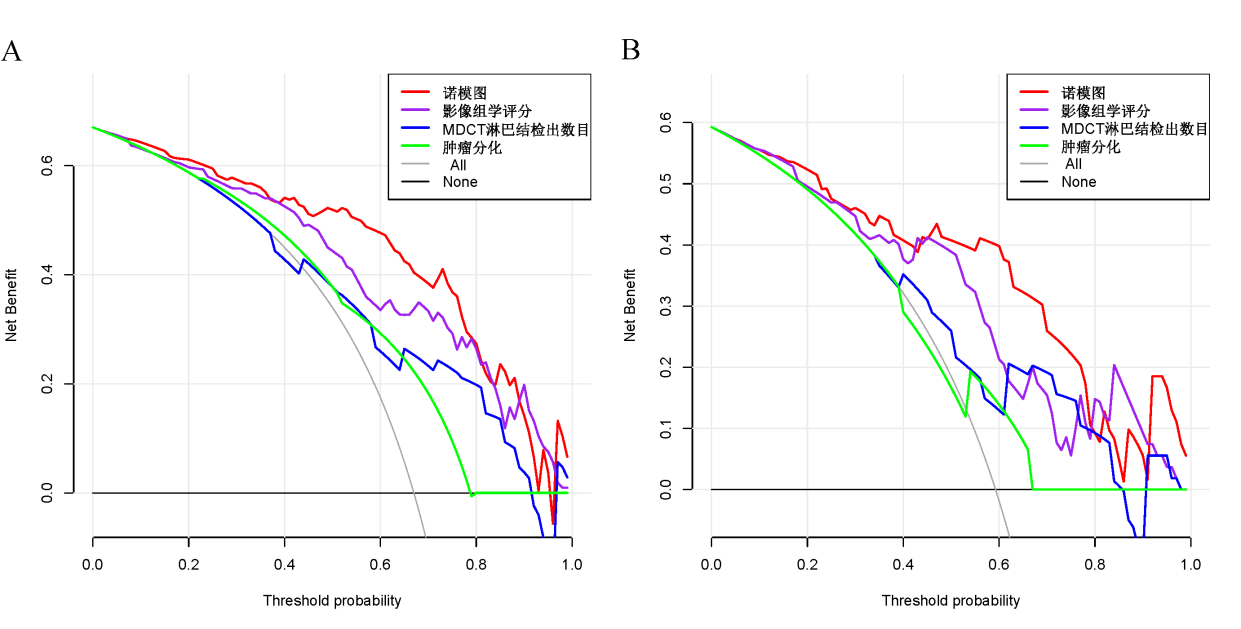

基于MDCT影像组学特征的模型对于预测胃癌淋巴结转移具有较高的准确度��,可为胃癌的个体化诊治提供基础信息����,有助于提高对临床决策的信心����。此外���,基于影像组学的模型还具有对胃癌患者预后分层的潜力���。

图7 (A)训练队列和(B)验证队列四种模型的决策曲线分析